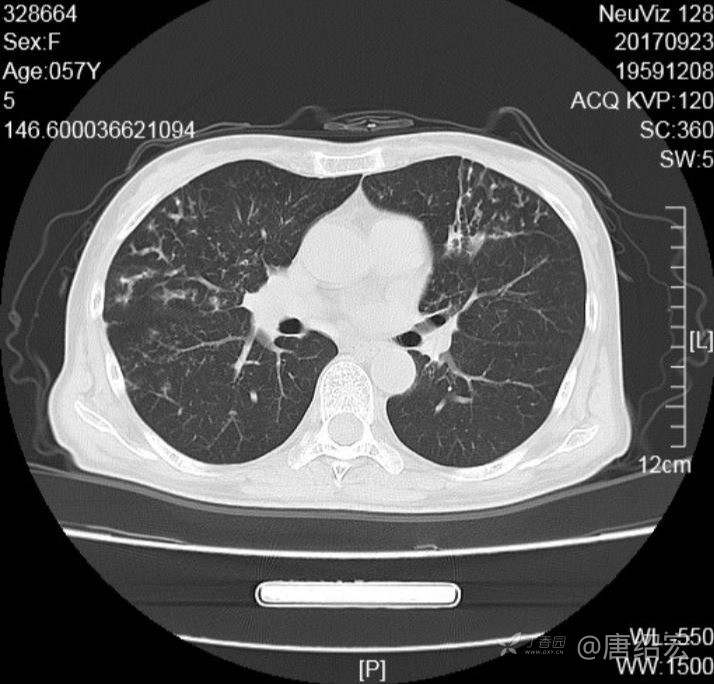

中年女性满肺树芽征还有支气管扩张,考虑什么疾病?

女,57岁,

主诉:发热、咳嗽、咯黄痰,胸闷3天入院。